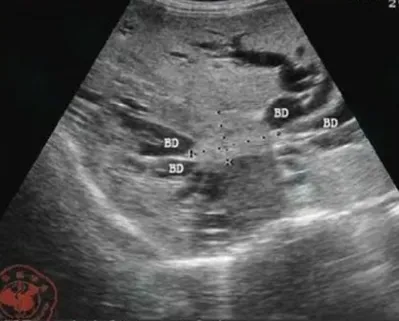

交通性海绵状胆管扩张(Caroli病)

● 定义:指肝内末梢胆管的葡萄串样囊状扩张,定义为肝内胆管非梗阻性节段性的囊状或梭状扩张,不伴有胰胆管合流异常。

● 超声表现:肝内沿胆管走行分布、多发的与胆管相通的无回声,可以弥漫性,也可以局限性的;特征性的表现为囊状扩张的胆管内见小圆点状高回声。